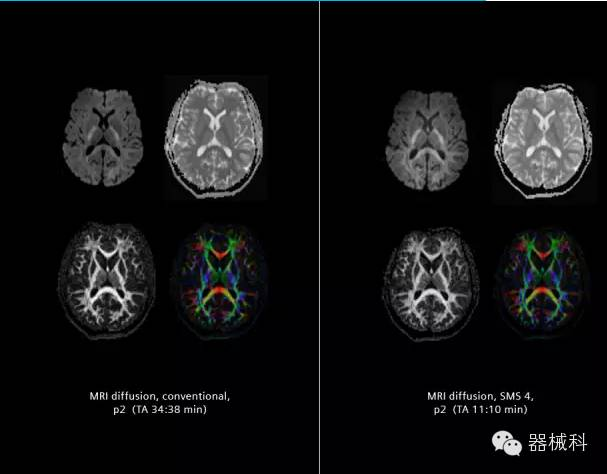

在2015年RSNA上,西門子隆重發(fā)布了Simultaneous Multi-slices 技術(shù)(即同時多層采集技術(shù),簡稱SMS),這是磁共振掃描技術(shù)中第一次引入“同時多層”的概念,此概念技術(shù)的發(fā)布,將對未來磁共振成像領(lǐng)域帶來巨大的變革!

SMS技術(shù)可以將原本用于科研的高級成像技術(shù)轉(zhuǎn)化成臨床常規(guī)。

擁有了SMS“同時多層”采集技術(shù)之后,用戶可以在非常短的時間內(nèi)完成MR掃描,結(jié)合西門子靜音技術(shù),大大提高患者的舒適性,或在單位時間內(nèi)采集更多的數(shù)據(jù),也可以得到高精度、高準確性、大數(shù)量的功能成像數(shù)據(jù),為臨床和科研提供強大的支持。專家認為,SMS“同時多層”采集技術(shù)未來在 提高成像質(zhì)量、外科手術(shù)計劃、降低術(shù)后神經(jīng)功能缺陷、提高fMRI的時間采集效率、提高靜息態(tài)功能磁共振數(shù)據(jù)質(zhì)量等方面將帶來深遠影響,希望該技術(shù)可以盡早面世,引領(lǐng)磁共振進入多層時代!